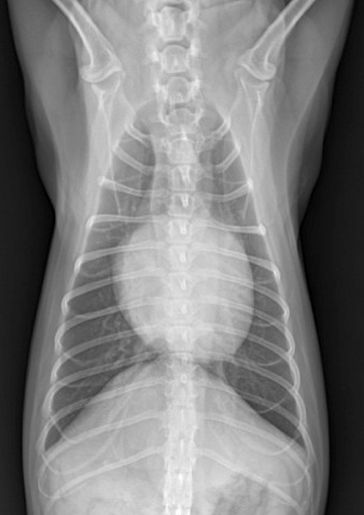

| 1기 (Moderate : 좌심방귀 볼록한 정도) |

| 1) 심장 커짐 Cardiomegaly, left auricle 확장, 전허리/후허리 소실 : 심장이 부풀면서 일자형이 됨. + Sternal contact : 심장과 sternum 거리 좁아짐 2) 기관에 영향 좌심방 비대 ⇒ 기관 상승, carina를 눌러서 기침 유발 (주로 밤에 기침) : tracheal elevation, bronchial collapse, noctural cough |